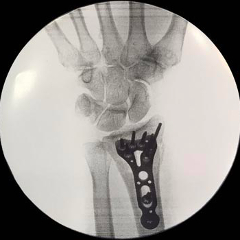

An incision is made in the forearm near the wrist. The broken bones are then exposed and aligned. Metal plates and screws are used to hold the bones in place. X-rays are then used to verify proper alignment and hardware placement.

Repair of Distal Radius Fracture Lateral View